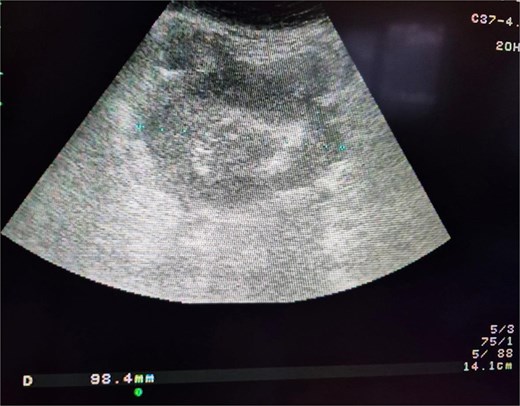

A 74-year-old woman complains of severe constipation, difficult to respond to laxatives and abdominal pain, nausea. A primary abdominal ultrasound (US) examination revealed a hypoechoic tumor formation in the lower abdomen, with uneven outlines and hyperechoic zones in it, with dimensions of ~10 cm/day (Fig. 1). The patient was referred for a computed tomography (CT) scan of the abdomen, which revealed a soft tissue formation with axial dimensions of 130/93 mm heterogeneous structure and infiltrative growth, affecting a segment of the ileum and an adjacent dilated small intestinal loop (Fig. 2). Secondary dissemination along the peritoneum with many soft tissue formations of different sizes formed in the abdomen and small pelvis. Identical lesions are described in the structures of both ovaries bilaterally, the larger of which is 47/34 mm/day. Laboratory parameters revealed anemia with values of Hg-103 g/L, and low values of total protein-60 g/L. The patient has a history of Hashimoto’s thyroiditis and is on replacement therapy with L-thyroxine. During hospitalization, she showed good compensation with a slightly increased TSH- 4.88 mU/L (normal 0.27–4.2) and normal FT4–17.7 pmol/L (normal 12–22). Tumor markers CEA, CA 125, and CA 19-9 were not elevated.